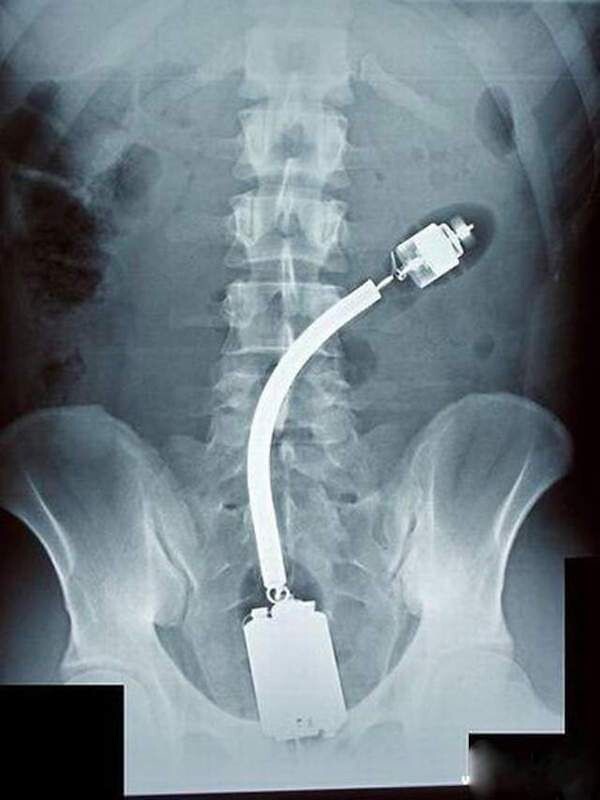

13. Що це таке і як воно туди потрапило?